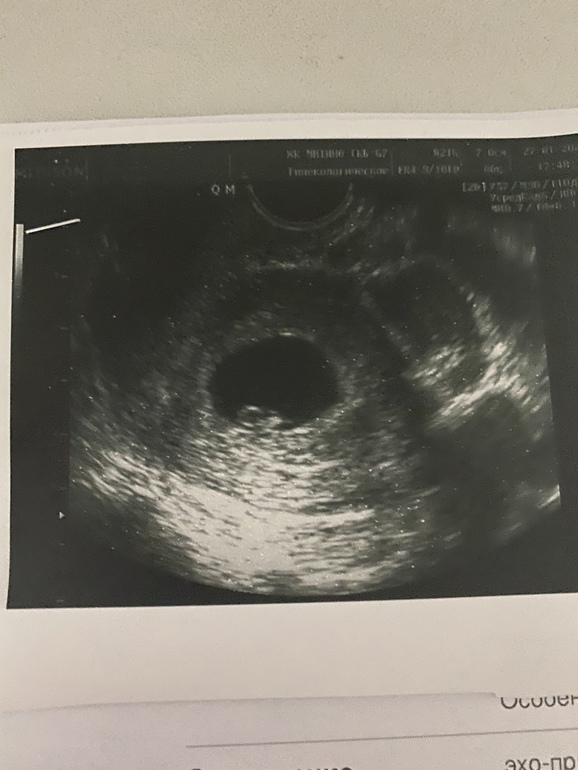

Начну с хорошего по узи 6+1, КТР 4,5 мм, сердцебиение есть, малышик соответствует сроку 💙🙏🏻